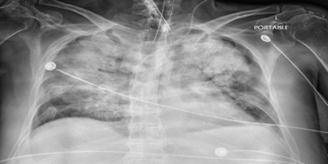

A 44-year-old male with a history of chronic alcohol use presented with a 7-day history of fever, myalgias, weakness, and progressive abdominal distention. On examination, he appeared icteric, with scleral icterus, left conjunctival suffusion, and ascites. Laboratory workup revealed severe hyponatremia (Na: 102 mEq/L), leukocytosis (WBC: 15.6 x10%L), and marked hyperbilirubinemia (total bilirubin: 16.5 mg/dL). A chest radiograph showed a patchy pneumonic process. Given his epidemiologic risk and clinical findings, leptospirosis was suspected. Empiric therapy with intravenous ceftriaxone and doxycycline was initiated, and Leptospira IgM testing was sent. Despite early antimicrobial treatment, the patient's condition deteriorated, requiring ICU transfer for septic shock management with vasopressors. Broad-spectrum antibiotics (vancomycin and piperacillin-tazobactam) were initiated. He subsequently developed worsening hypoxemic respiratory failure, necessitating mechanical ventilation. High-resolution CT of the chest demonstrated bilateral diffuse progression of multifocal ground-glass opacities, in the presence of worsening hemoptysis which is consistent with DAH (Figures 2 A / B). A bronchoalveolar lavage was subsequently performed, which confirmed the diagnosis. Ventilatory management included high PEEP, increased FiO2, and lung-protective tidal volumes. Adjunctive corticosteroid therapy was initiated. However, persistent bloody endotracheal secretions indicated ongoing alveolar bleeding, complicating ventilatory strategies. Prone positioning was employed as a salvage maneuver, but the patient's course was further complicated by multiorgan failure.

Figure 1A: Chest X-ray revealing bilateral diffuse, non-homogeneous fluffy opacities, along with lung infiltrates and haziness indicative of edema, hemorrhage, or pneumonia. Additionally, there is a small pleural effusion on the left side.